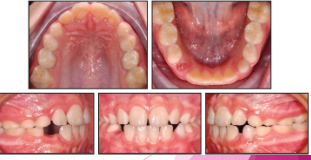

Normal eruption patterns

 As a permanent tooth develops, the root length increases and it moves into position by “pushing out” the primary tooth

 While this is happening, the primary tooth root starts to resorb and shorten

 What is happening in this radiograph?

 Primary molars

• Flared roots

• Resorption

 Permanent molars

• Straighter, longer roots

• Roots still forming

• Apical foramen open & wide

Follicular space

• RL area surrounding developing tooth

• Normal

<p><span> As a permanent tooth develops, the root length increases and it moves into position by “pushing out” the primary tooth </span></p><p><span> While this is happening, the primary tooth root starts to resorb and shorten </span></p><p><span> What is happening in this radiograph? </span></p><p><span><strong> Primary molars </strong></span></p><ul><li><p><span>Flared roots </span></p></li><li><p><span>Resorption<strong> </strong></span></p></li></ul><p><span><strong> Permanent molars </strong></span></p><ul><li><p><span>Straighter, longer roots<strong> </strong></span></p></li><li><p><span>Roots still forming </span></p></li><li><p><span>Apical foramen open &amp; wide<strong> </strong></span></p></li></ul><p><span><strong>Follicular space </strong></span></p><ul><li><p><span>RL area surrounding developing tooth </span></p></li><li><p><span>Normal<strong> </strong></span></p></li></ul><p></p>

Dental charting

knowt flashcard image